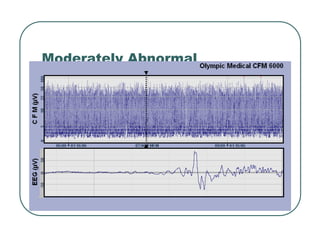

Moderately Abnormal

Seizure EEG

DeVries

DeVries L,

L, Toet

Toet M, Clin. Perinatol., 2006

M, Clin. Perinatol., 2006

Term infant with middle cerebral artery infarct